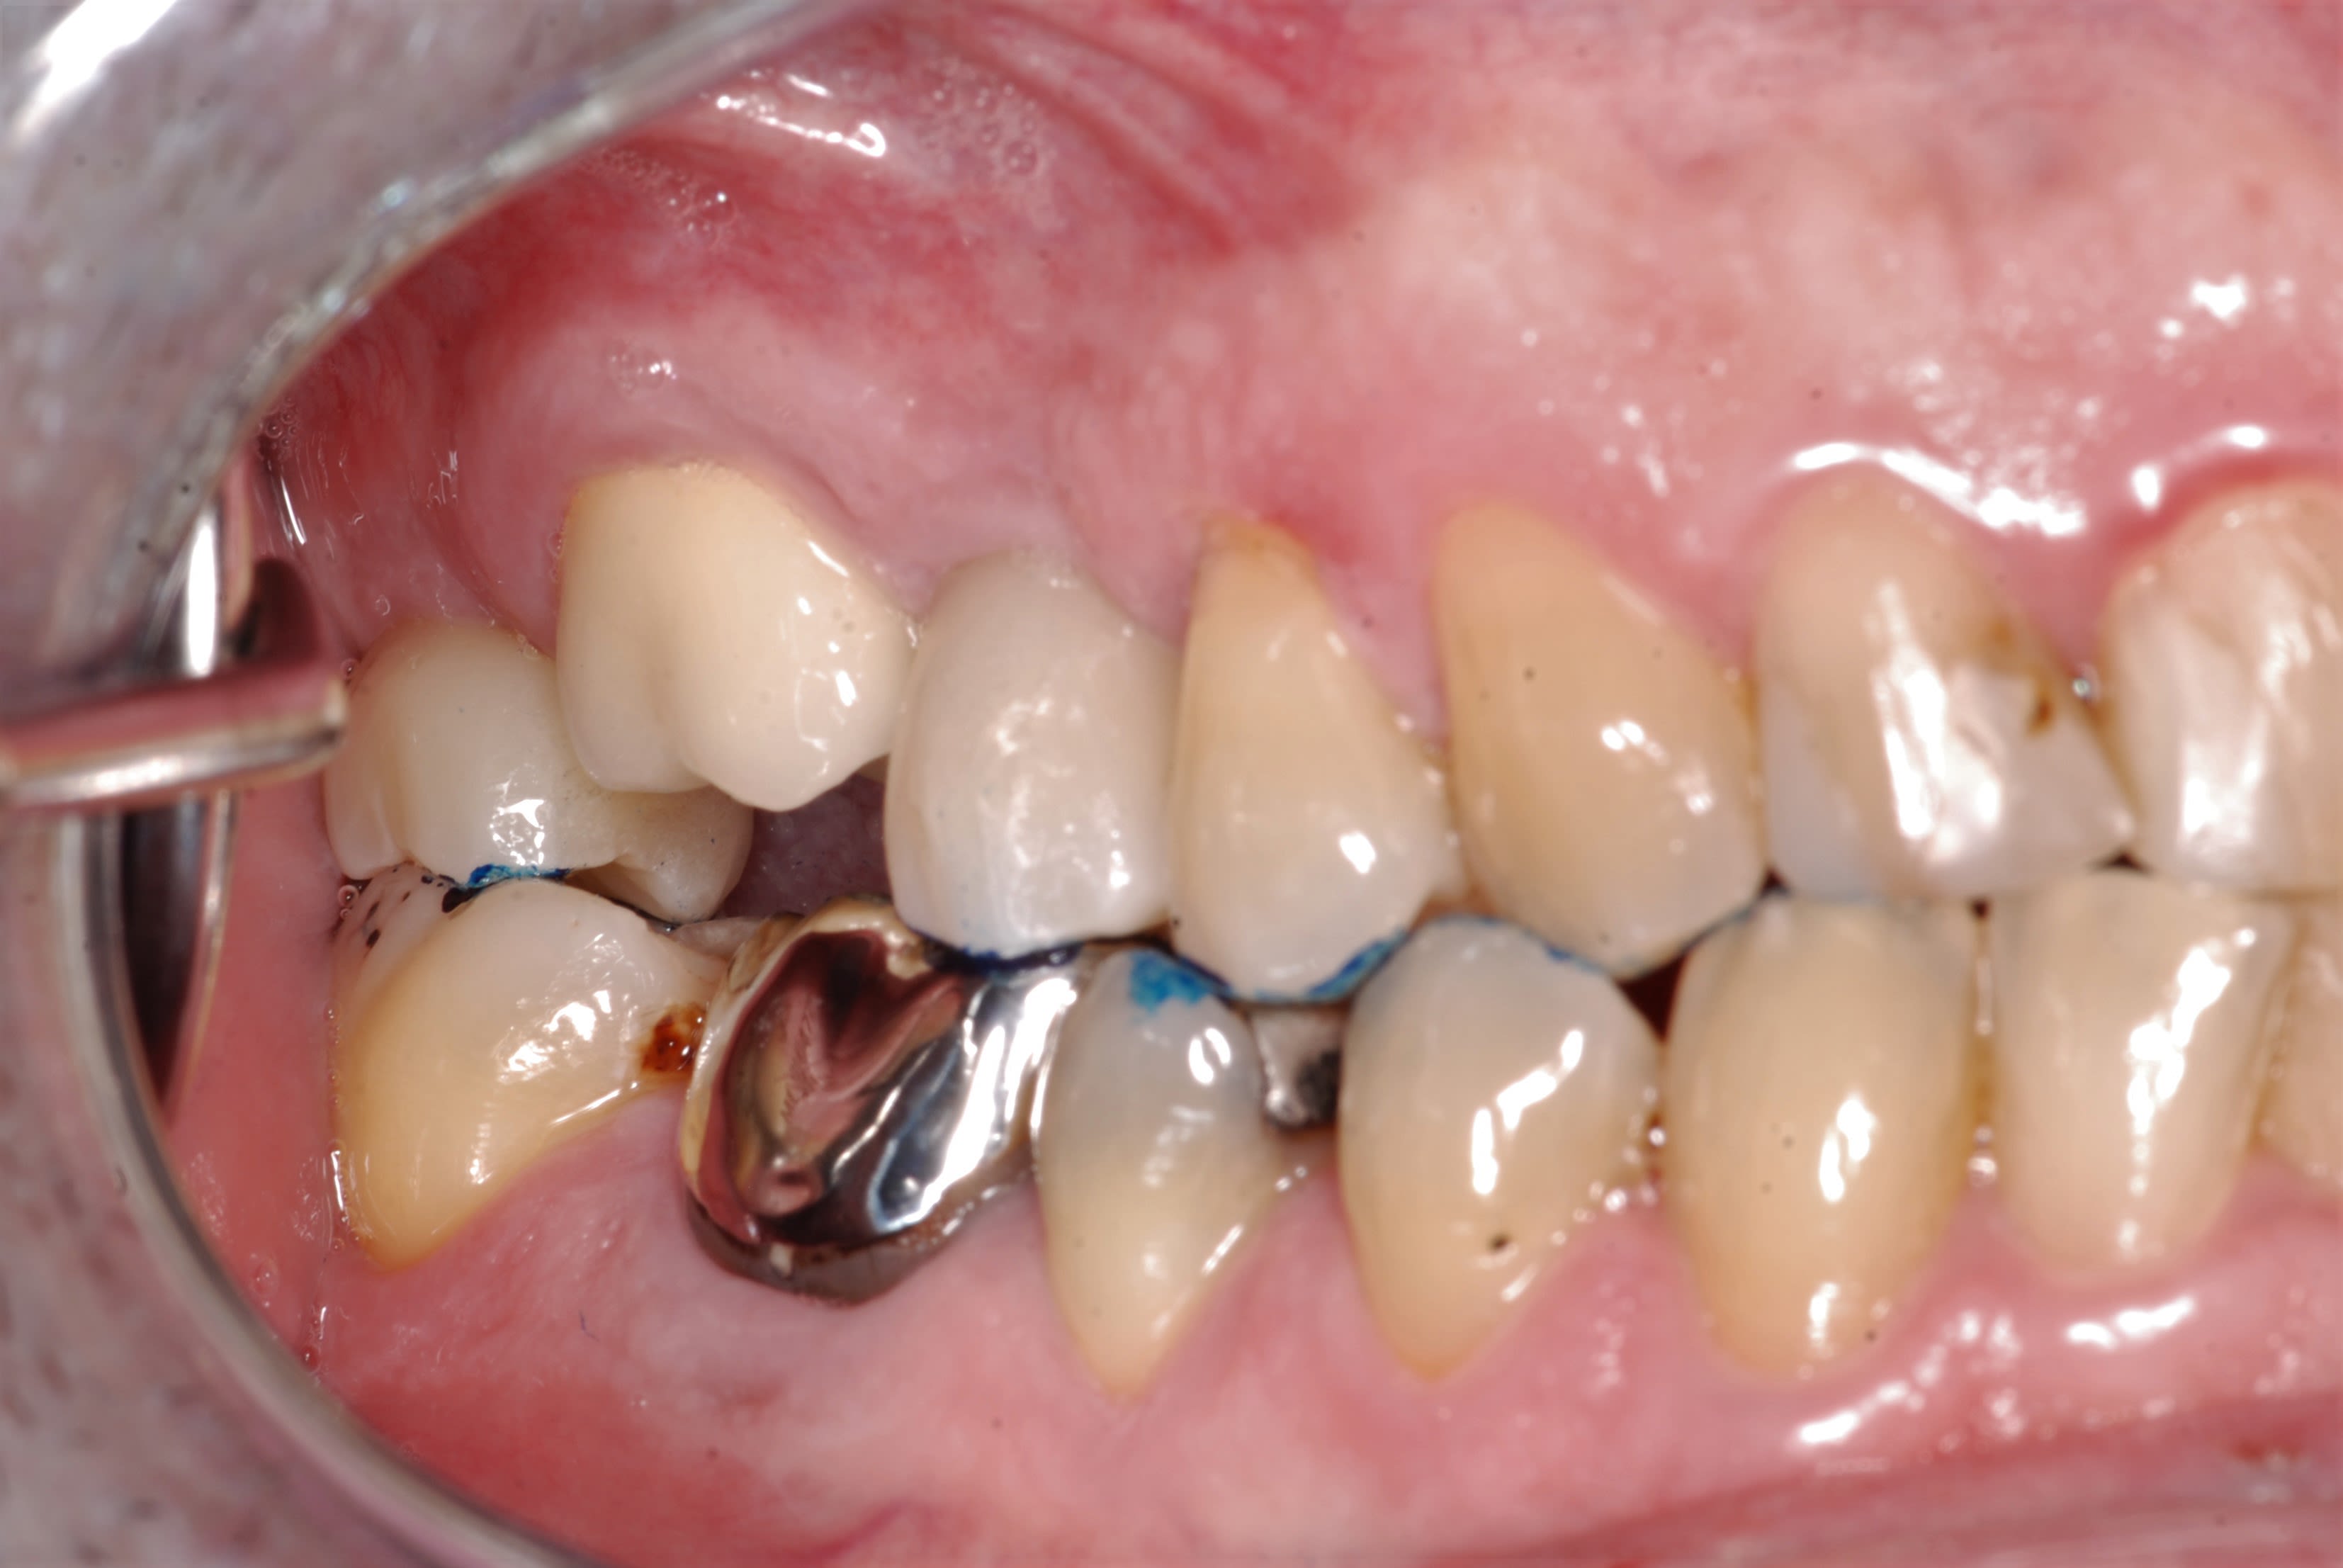

Comme promis, voici les photos du cas.

Comme je disais on dirait que la dent est remontée avec tout son parodonte...

Rien de particulier de noté au cbct fait par mon correspondant implanto. je vais lui demander les coupes

pourtant , sa couronne "fer" est toute mate en distal , pourquoi ? on dirait qu il y a ou qu il y a eu frottement mais pas avec un truc dur . .

et sa ceram , elle est cassée en distal ?

Si les points de contact sont serrés, je ne comprends même pas comment la couronne a pu être mise en place: nous sommes au-delà de la ligne de plus grand contour!

Je rappelle que les deux adjacents sont sur implant, impossible de jouer sur le ligament popur passer en force.